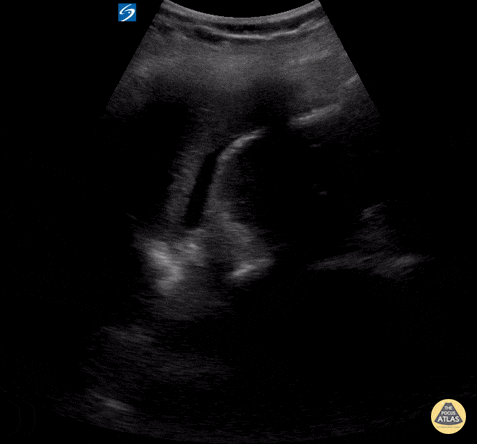

Peds-Trauma

abnormalluq, abnormalruq, msk, traumanormal